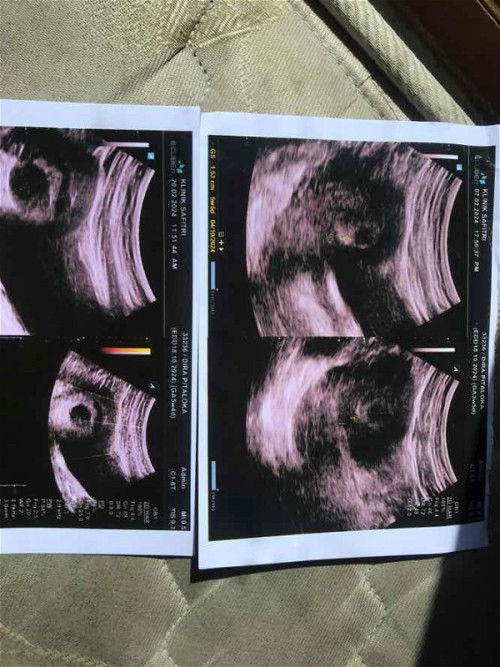

5-6w Hanya terlihat kantung kehamilan saja

Bun ada gak disini yang USG usia kehamilan 5-6minggu? Apakah udah terlihat bakal janinnya sama djjnya? Soalnya punyaku hanya keliatan kantung kehamilan aja. Dokter menyarankan kuret karna takutnya BO Tapi aku masih gamau, dan minta nunggu lagi sampe 9-12w USG lagi. Ada yang punya pengalaman serupa gak ya?#bantujawab #bantusharing #sharing #hamil6week #ingintahu